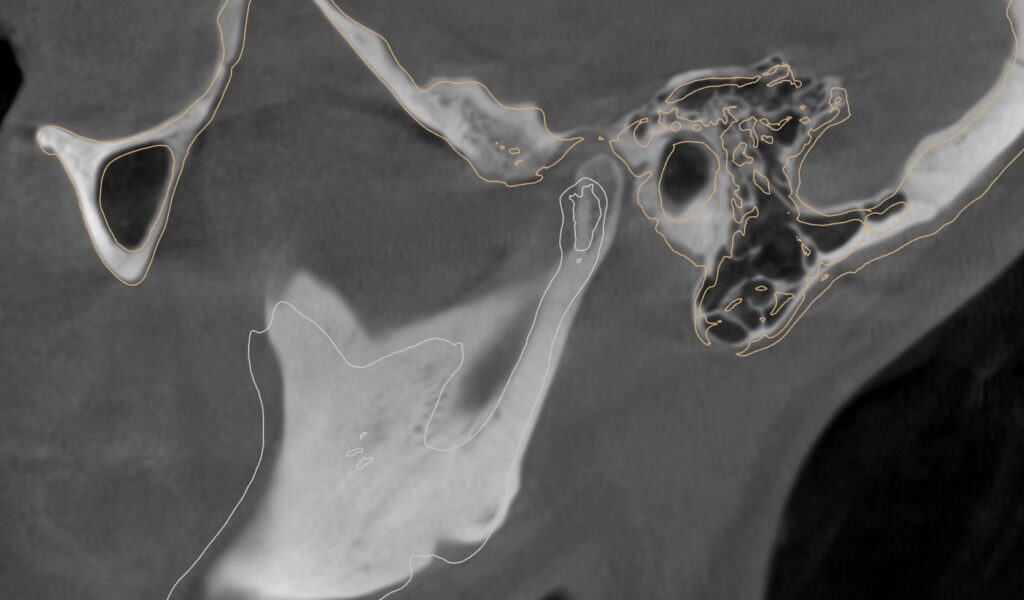

Prin suprapunerea structurilor osoase, a dinților și a modelului mandibular (MODJAW), putem vizualiza traseul și poziția condilului în fosa articulară. Pe baza acestei analize, stabilim poziția terapeutică a mandibulei, care devine reperul pentru realizarea designului gutierei.